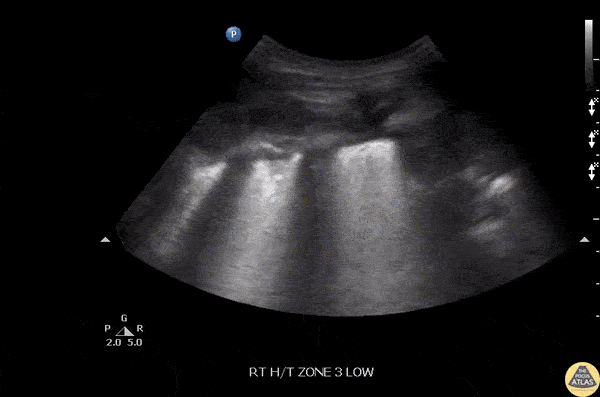

Pulmonary - Pnuemonia-Thickened Pleura

Increased thickness of the pleura with diffuse B-lines can be seen in this patient with pneumonia. Image courtesy of Robert Jones DO, FACEP @RJonesSonoEM Director, Emergency Ultrasound; MetroHealth Medical Center; Professor, Case Western Reserve Medical School, Cleveland, OH View his original post here